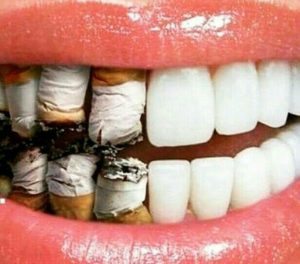

pone de ninguna evidencia científica que permita avalar el uso de estos productos como sustituto o complemento de la higiene oral. Desde nuestra clínica dental, solamente podemos apoyar técnicas que se fundamentan en principios científicos y que cuentan con aval suficiente sobre su eficacia y seguridad. Así que la respuesta del experto es una negativa rotunda. Con los productos milagrosos, como el agua de coco, hay que ser prudentes. as patologías de la boca. El café tampoco ha demostrado ser un agente saludable en ese terreno. Por lo tanto, y al igual que otras organizaciones médicas y odontológicas internacionales, solo podemos recordar que se debe hacer un consumo moderado de estos productos. Además, tanto el café como el vino o algunos refrescos que pueden acompañar a bebidas alcohólicas no son solo perjudiciales para la salud de la boca, sino también para su estética, y tienden a amarillear la dentadura.

as patologías de la boca. El café tampoco ha demostrado ser un agente saludable en ese terreno. Por lo tanto, y al igual que otras organizaciones médicas y odontológicas internacionales, solo podemos recordar que se debe hacer un consumo moderado de estos productos. Además, tanto el café como el vino o algunos refrescos que pueden acompañar a bebidas alcohólicas no son solo perjudiciales para la salud de la boca, sino también para su estética, y tienden a amarillear la dentadura. cía hacía el diente y no al revés». Por último, no hay que olvidarse de la lengua, que es un foco de placa bacteriana y se debe cepillar de dentro hacia fuera. Pero, sobre todo, lo importante es hacerlo a menudo: si puede ser,después de cada comida. Y que la pereza no pueda con el último cepillado del día.